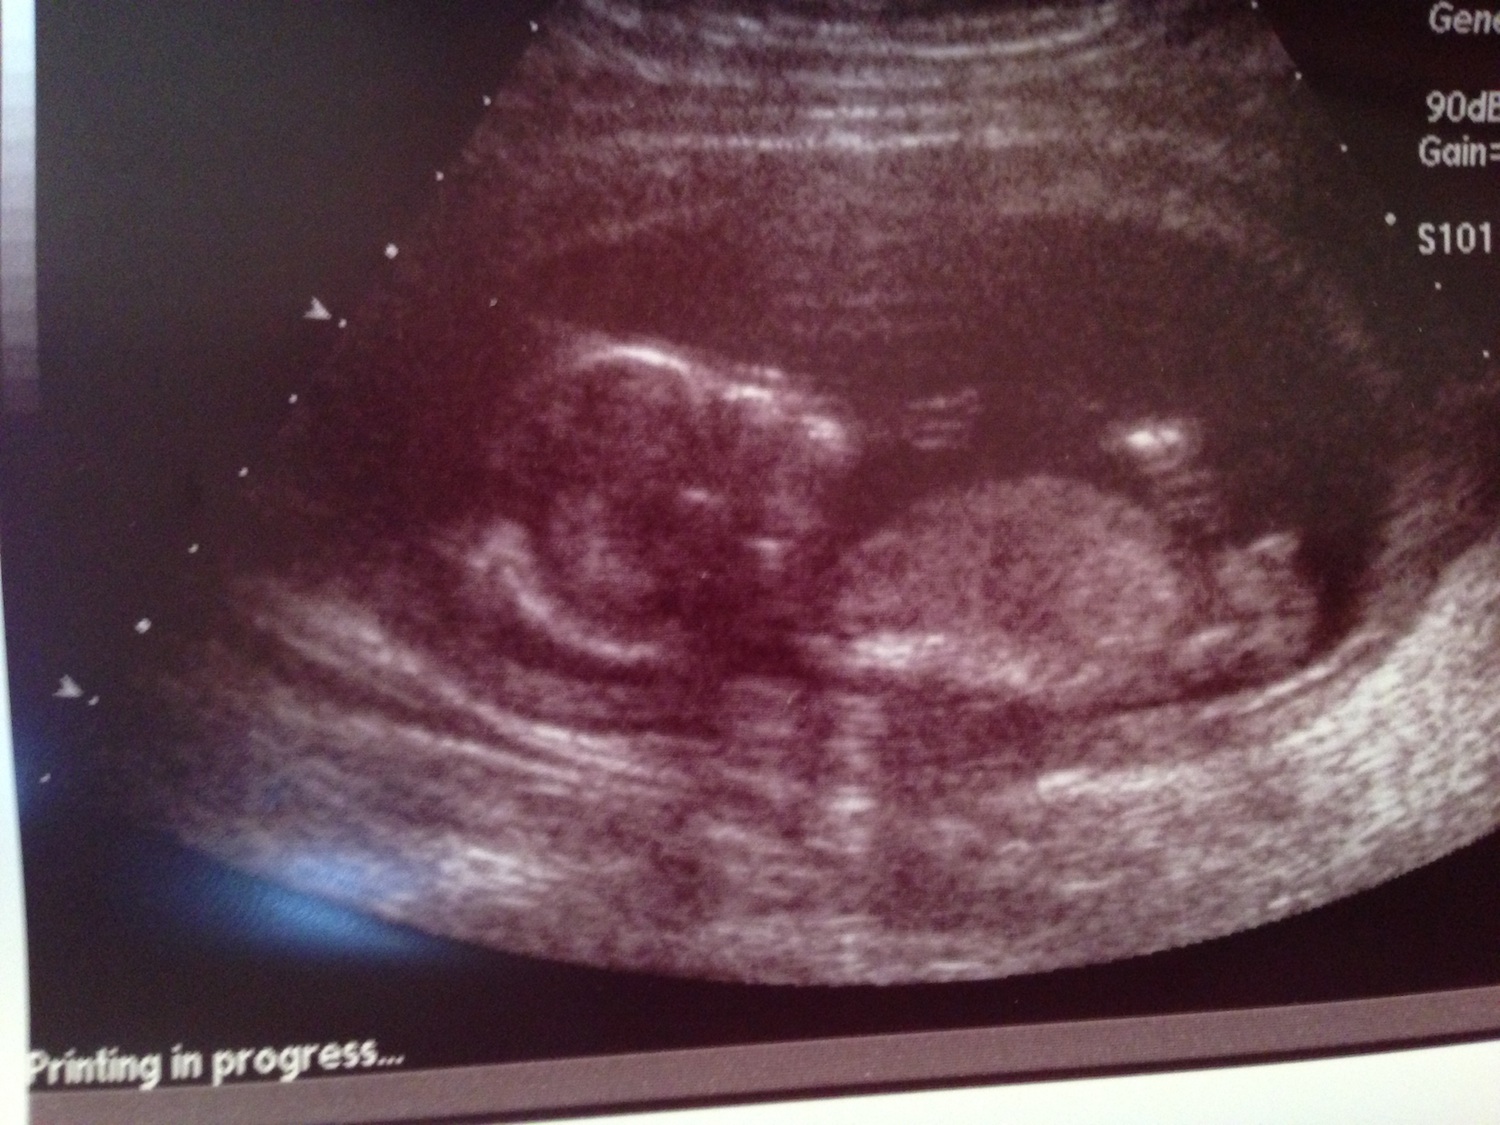

Ok I think I see what you are saying. I added a second image to show you what I believe you are explaining. As you can tell this is my first pregnancy :happy: and i'm probably asking stupid questions! Again thank you for helping me. If you do come across a 15 week profile please let me know.

Attachment 10742

Yes, that is the scrotum and the other arrow that was already on the image is pointing to the penis.

Ok thank you so much I finally see it!! So at 15 weeks would the penis be vertical or is it still valid to measure it against the spine?

At 15 weeks you wouldn't measure the angle of a boy anymore--it just wouldn't be necessary as it is VERY different from a side shot of a girl. Only inexperienced guessers would get them confused. Hope that helps :)